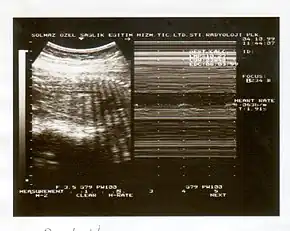

A biophysical profile (BPP) is a prenatal ultrasound evaluation of fetal well-being involving a scoring system,[1] with the score being termed Manning's score.[2] It is often done when a non-stress test (NST) is non reactive, or for other obstetrical indications.